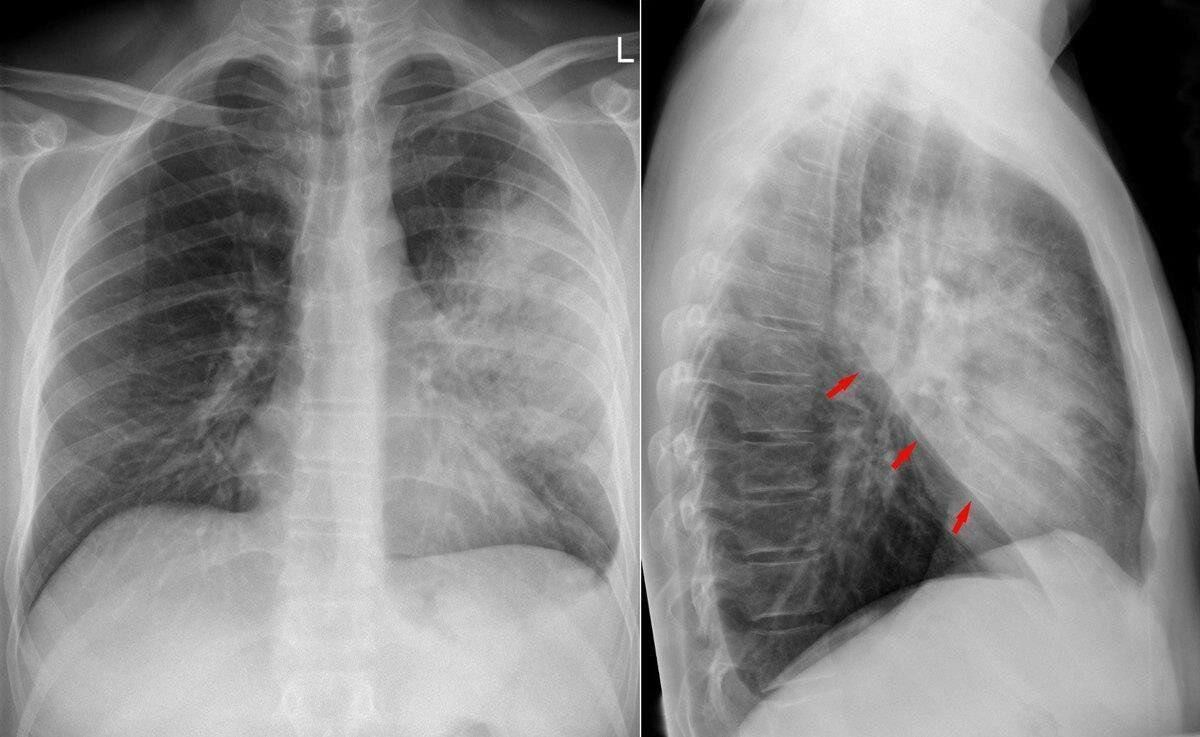

Отмечается, что новая технология анализирует рентгеновские снимки с помощью компьютерного зрения, определяя наличие заболевания с точностью до 90 процентов.

«Мне удалось построить 20 разных моделей и сравнить множество архитектур глубокого обучения, чтобы использовать их в работе с рентгеновскими снимками. Был проведен сравнительный анализ множества моделей, включая классические алгоритмы и современные архитектуры нейросетей. Такой подход позволил определить наиболее эффективное решение, учитывающее особенности медицинских изображений, что редко встречается в подобных исследованиях. Так, наиболее эффективные модели для решения задачи диагностики продемонстрировали точность более 90%. Например, получилось добиться 94 процентов точности при помощи модели Inception и 93,2 процента при помощи модели MobileNet», – объяснила Раскопина.